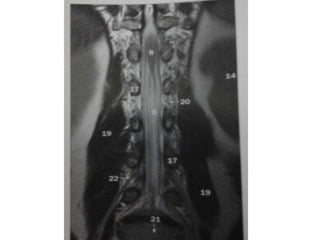

The images are of a child . The images are non-specific with multiple focal lesions and probably

the first choise would be MS.

The differential diagnosis would include inflammation, infection and metastases.

In such cases always perform a transverse image of the spine to look for the exact location and

perform a MRI of the brain.

The lesions are located dorsally and one of the lesions is enhancing.

Now if this was infection or metastases it would be strange that not all lesions enhance.

MS is still on our list.

On the CE-T1WI only one lesion shows enhancement.

The location of the lesions and the enhancement could very well fit to the diagnosis of MS, but

this proved to be vasculitis.